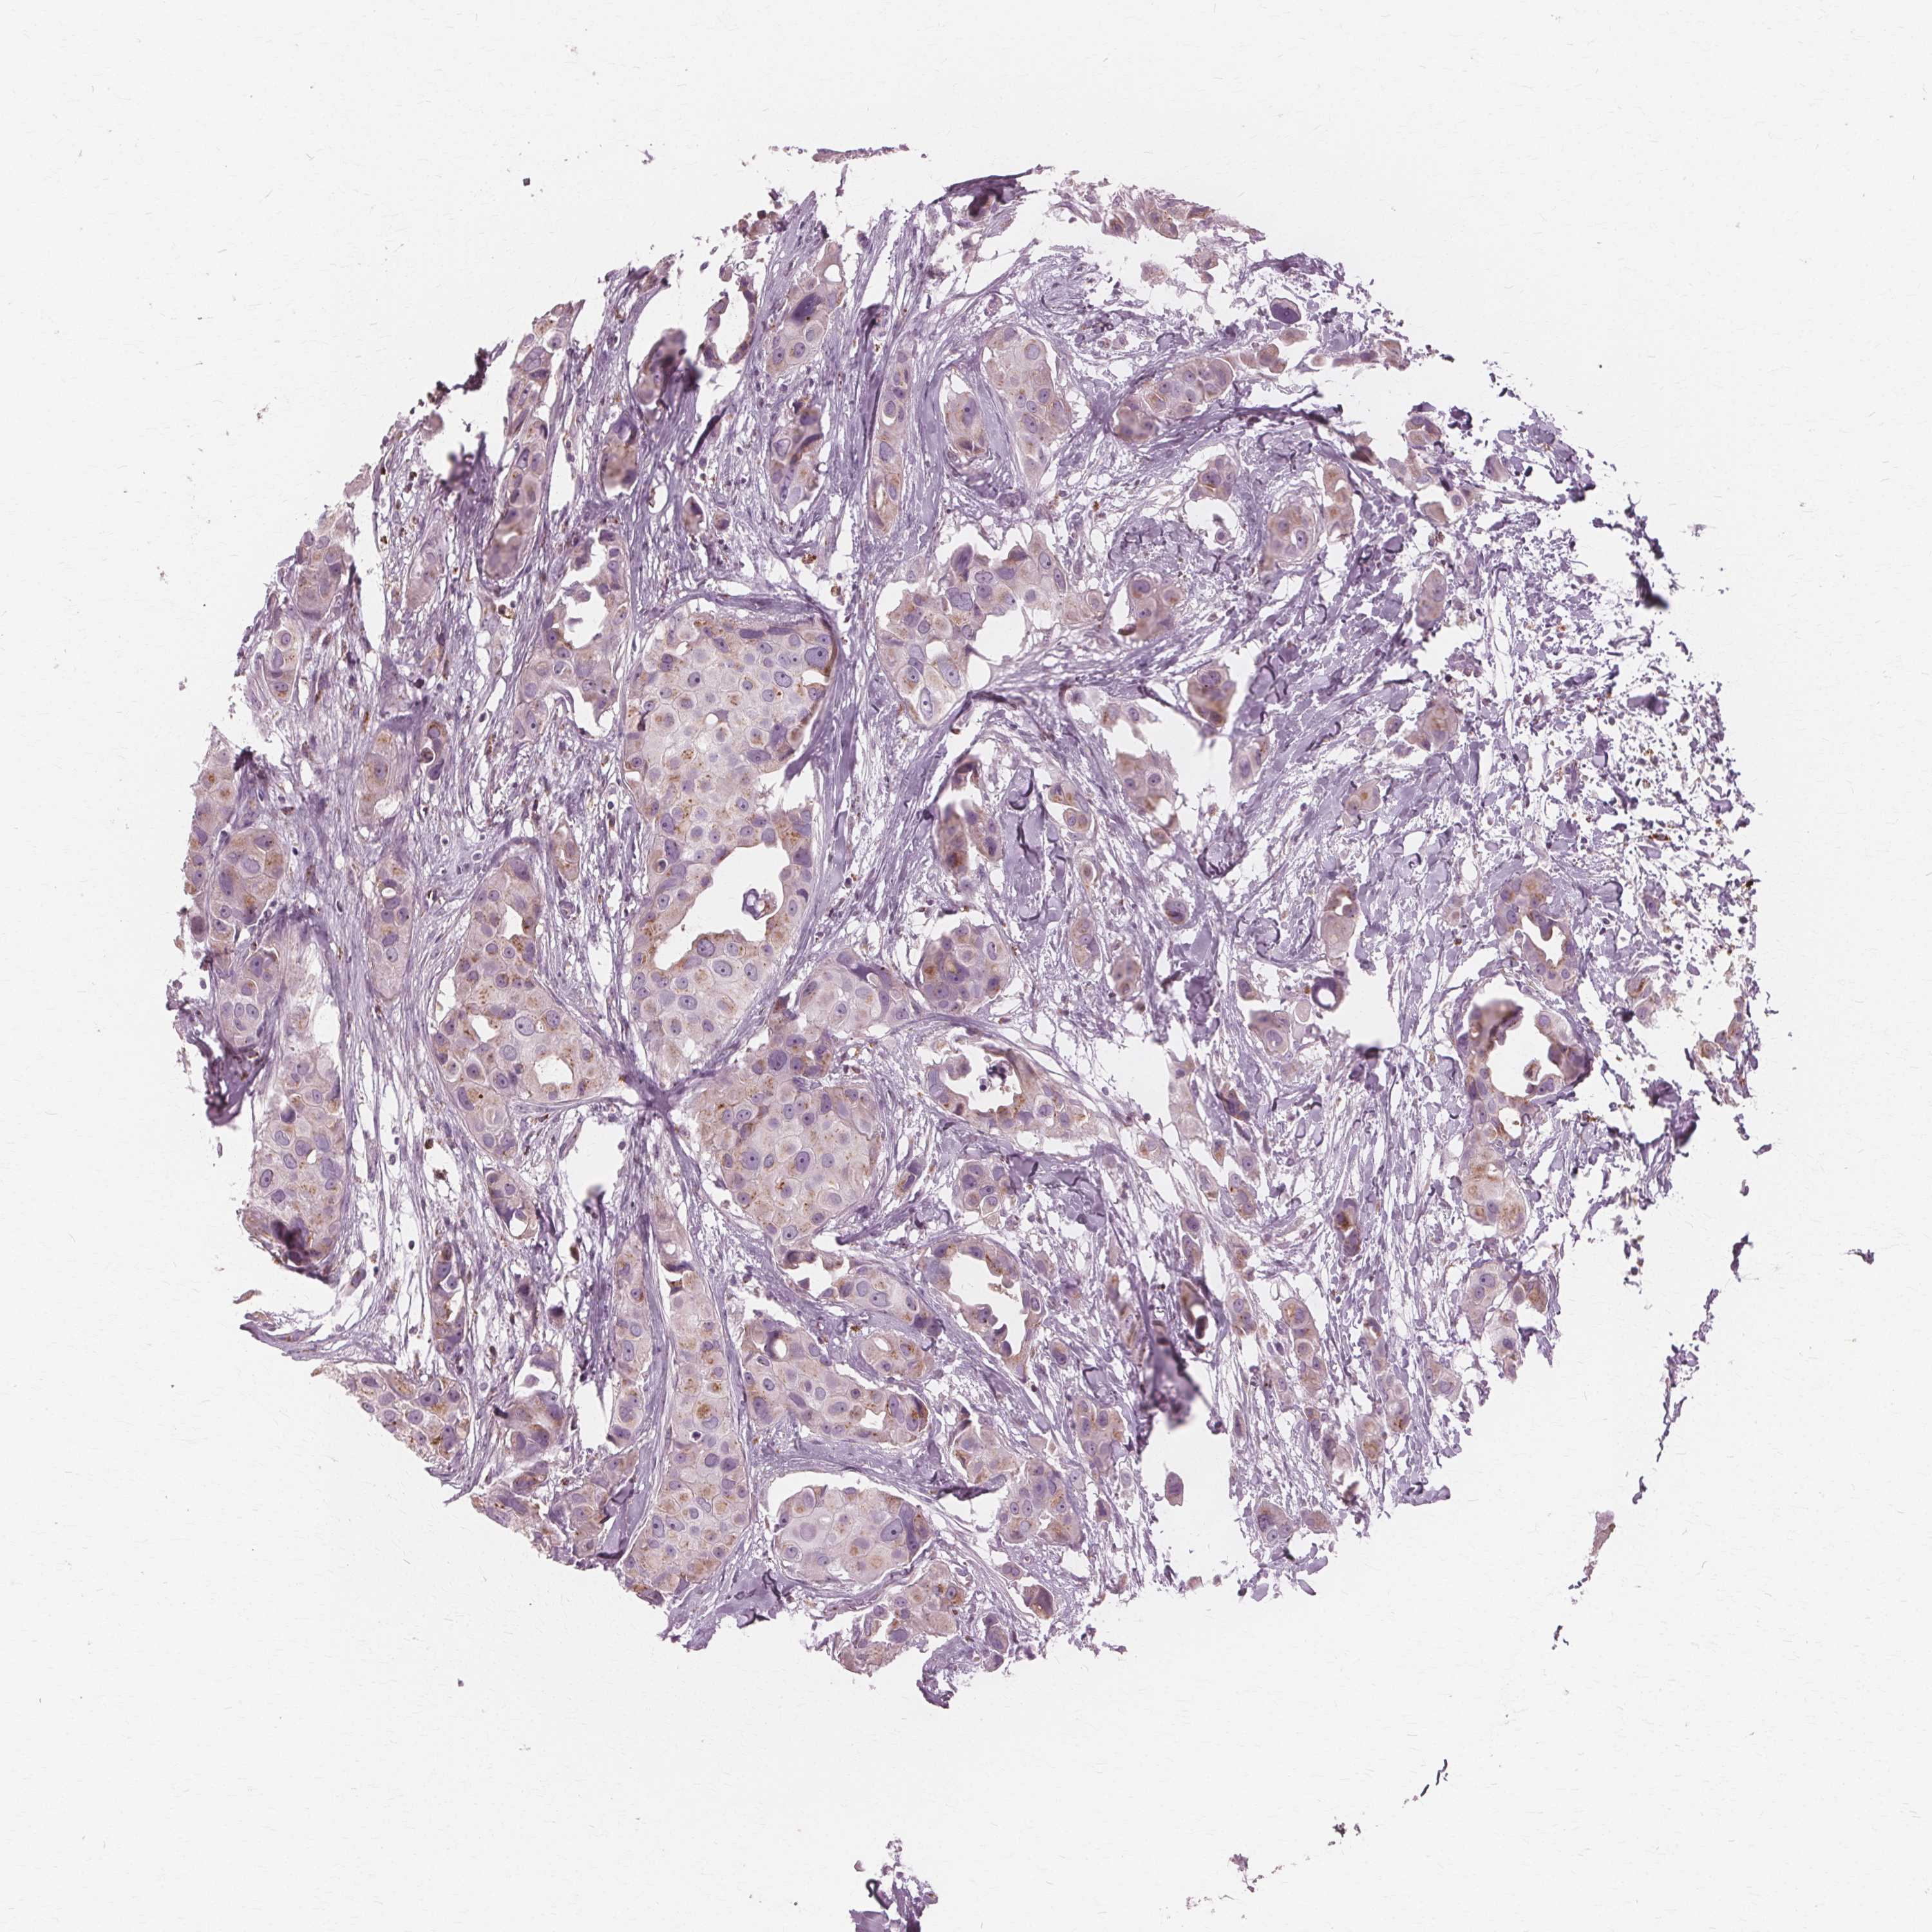

BRCA TCGA BRCA VALIDATION PROTEIN EXPRESSION

Breast cancer

Human cancer